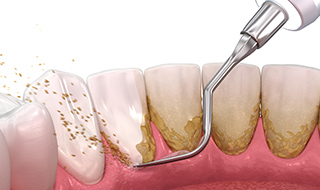

歯周病の治療の流れ

1

検査①

歯周ポケットの深さの確認、レントゲン撮影などお口の検査を行います。

2

歯周基本治療

原因である歯垢の除去、歯根面の滑択化などを行います。

3

検査②

STEP2により、歯周組織が改善した場合はメインテナンスに移行します。改善が見られない場合はSTEP4でSRPを行います。

4

SRP

スケーリング・ルートプレーニングという歯石除去処置を行います。歯周ポケットの中の歯垢や歯石まで除去できます。

5

メインテナンス

定期的に通院していただき、歯や歯ぐきの状態を確認していきます。合わせて歯のクリーニングやブラッシング指導を行います。